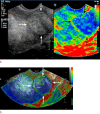

Diagnostic ultrasound (DUS) is, arguably, the most common technique used in obstetrical practice. From A mode, first described by Ian Donald for gynecology in the late 1950s, to B mode in the 1970s, real-time and gray-scale in the early 1980s, Doppler a little later, sophisticated color Doppler in the 1990s and three dimensional/four-dimensional ultrasound in the 2000s, DUS has not ceased to be closely associated with the practice of obstetrics. The latest innovation is the use of artificial intelligence which will, undoubtedly, take an increasing role in all aspects of our lives, including medicine and, specifically, obstetric ultrasound. In addition, in the future, new visualization methods may be developed, training methods expanded, and workflow and ergonomics improved.